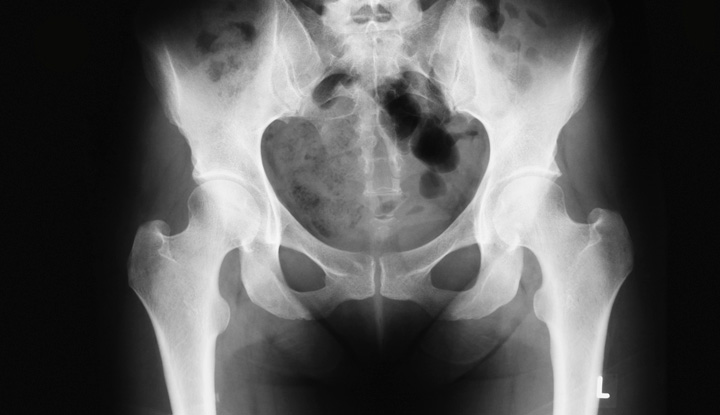

Estudios radiológicos con tecnología digital y mínima exposición a radiación.

Servicio de Rayos X

En Clínica Nuestra Señora de Guadalupe contamos con equipo de Rayos X digital, que nos

permite realizar estudios con alta calidad diagnóstica. Con este sistema, el médico radiólogo

puede llevar a cabo diversos procesos de imagen, como la utilización de zoom, la toma de

mediciones de lesiones, medidas cardiotorácicas, cálculos de ángulos para estudios de

ortopedia, inversión de imágenes, aplicación de filtros para mejorar la toma radiográfica o para

disipar dudas en cuanto a la etiología de las lesiones que pudiesen observarse.